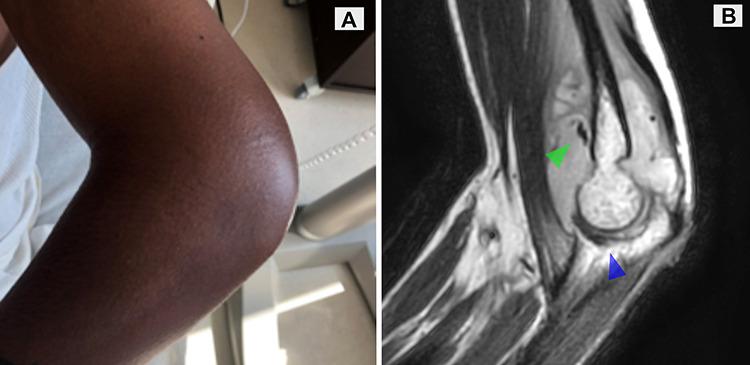

Osteoarticular tuberculosis involving the elbow.